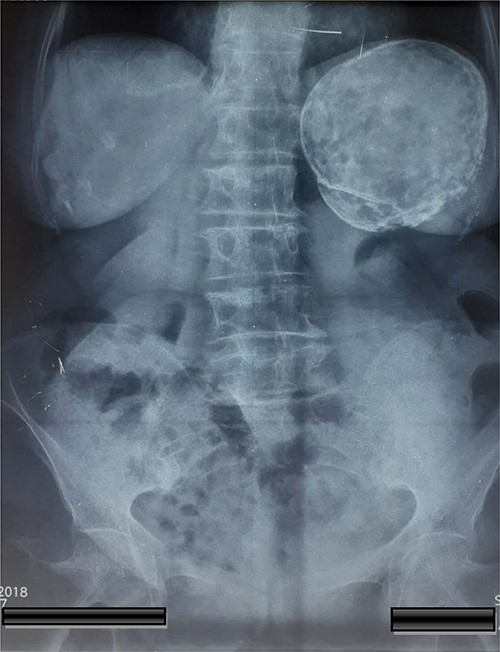

A 74-year-old woman was admitted to the internal medicine ward due to cough, pain and heaviness in the left upper abdominal quadrant. Pain was localized to the left upper abdominal quadrant, and it intensified within the last 2 months. The laboratory test results were normal. However, physical examination revealed tenderness upon palpation in the left upper quadrant and splenomegaly. Moreover, thoracic and abdominal radiography revealed an egg shell-like calcified well-circumscribed ovoid mass at the left upper abdominal quadrant (Fig. 1). Computed tomography (CT) scan of the abdomen revealed a 10.5 × 9.6 × 9.5-cm ovoid splenic cyst with peripheral rim calcification. The cyst had homogeneous internal substance with no prominent daughter cysts or scolices (Fig. 2). Thoracic and abdominal CT-scan did not reveal other pathologies and cystic lesions. The patient underwent exploratory laparotomy. Then, a splenic cyst was observed, and the spleen was found to be densely adherent to the diaphragm and gastrosplenic ligament. A laparotomy was performed and the spleen with the cyst was removed without opening. A well-described accessory spleen with a diameter of 8 mm was found in the gastrosplenic ligament. The splenectomy specimen and the accessory spleen weighed 320 g and 4 g, respectively (Fig. 3), and they were sent for histopathological examination. The patient’s postoperative recovery was uneventful. She was discharged on the sixth postoperative day and treated with albendazole for 3 months.

CT of the abdomen shown a 10.5 × 9.6 × 9.5-cm ovoid splenic cyst with peripheral rim calcification.